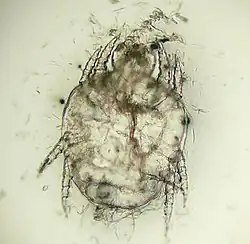

| Cheyletiella yasguri (?) from a dog | |

The adult mites are about 0.385 millimeters long, have eight legs with combs instead of claws, and have palpi that end in prominent hooks.[5] They do not burrow into the skin, but live in the keratin level. Their entire 21-day life cycle is on one host. They cannot survive off the host for more than 10 days.[6]